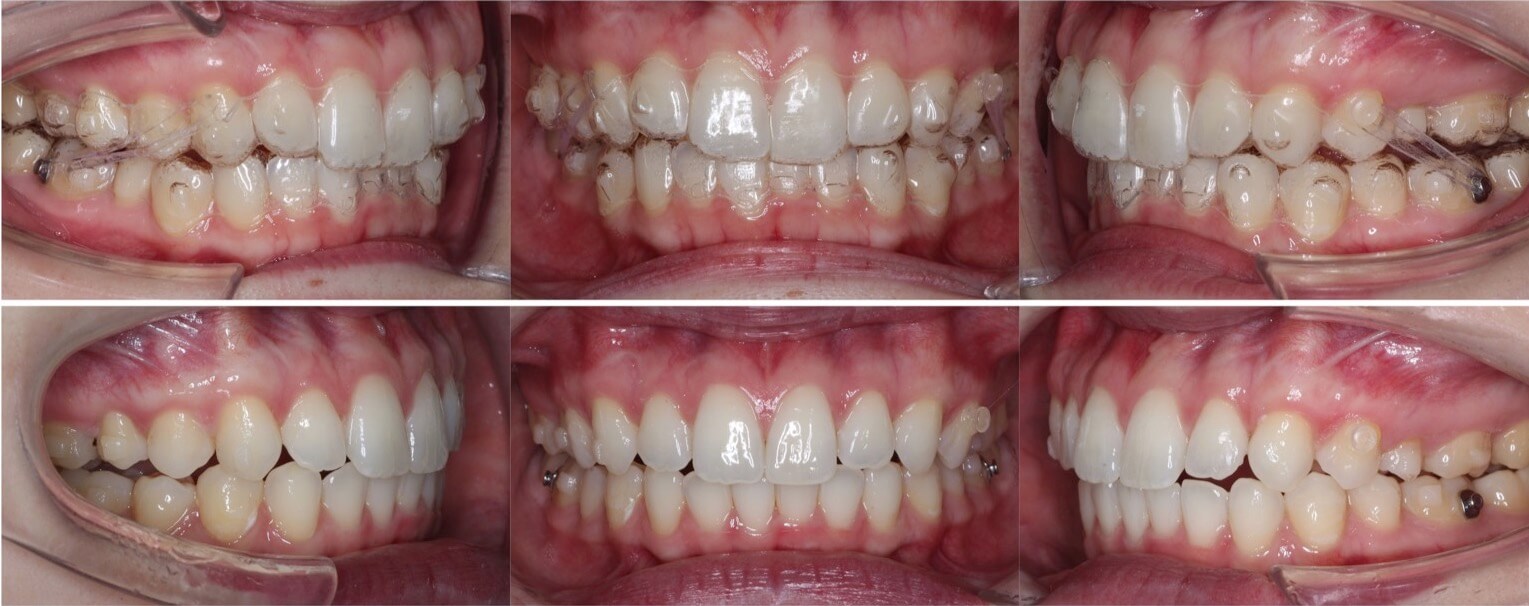

中学生女子・マウスピース型装置

典型的なII級2類と呼ばれる、過蓋咬合を伴う上顎前突症例です。10代前半であり下あごのかみ合わせがまだ定まっていなかったため、バイトウィングという下あごの前後的位置を調整するマウスピースを使用をして正しいかみ合わせに調整しました。内側に倒れていた上の前歯の向きも改善し、良いスマイルに変化しました。

<症例概要>

主訴:歯並びのがたつき

住まい:千葉県船橋市

年齢・性別:中学生女子

症状:上顎前歯舌側傾斜・過蓋咬合・上下顎叢生・アングルII級2類

治療方針:上顎前歯の前方傾斜移動・下顎の前方推進

治療装置:マウスピース型矯正装置(アライナー装置)

治療期間:1年11か月

アライナー枚数:36+38+27ステージ (7日交換)

リテーナー:上下フィックスタイプ+プレートタイプ

治療費用:990,000(税込)

代表的副作用:痛み・治療後の後戻り・歯根吸収・歯髄壊死・歯肉退縮

上の前歯を前方移動させることで、上下の前歯のロックを解除し、自然に下顎が前方移動するように誘導しています。